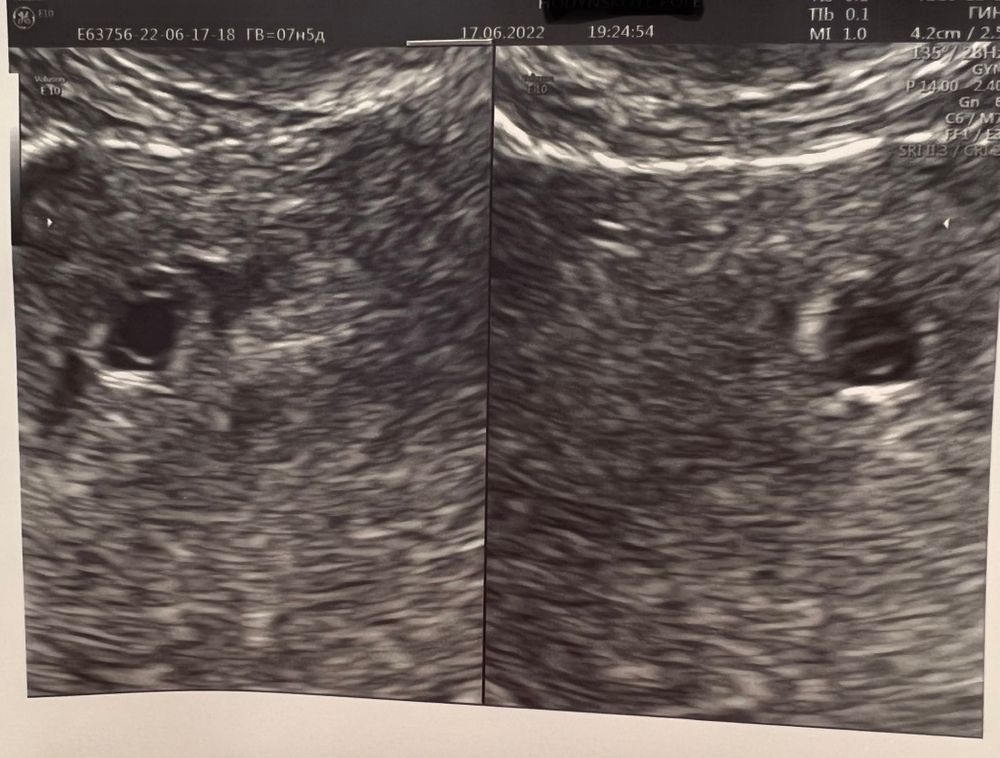

Помогите найти Желточный мешочек 🙏🏽😅

Пустотелый круг внутри плодного яйца. Как кольцо выглядит

Alena, да, должно быть как кольцо, но я его тут в упор не вижу😐